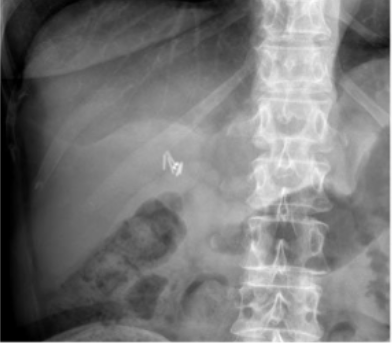

What is this and what type of scan

AAA, Abx